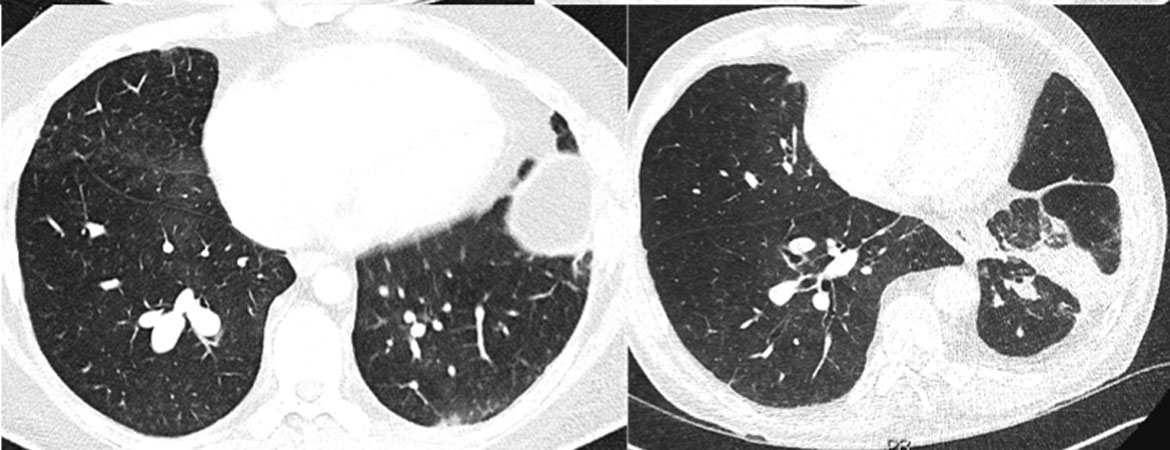

Seyed Mohsen Mousavi, Sabine Schmid, Thomas Cerny, Martin Früh (Author) Lung cancer and smoking trends in the young in Switzerland: a study based on data of the National Institute for Cancer Epidemiology and Registration and of the Swiss Health Surveys Fulltext PDF Fulltext HTML